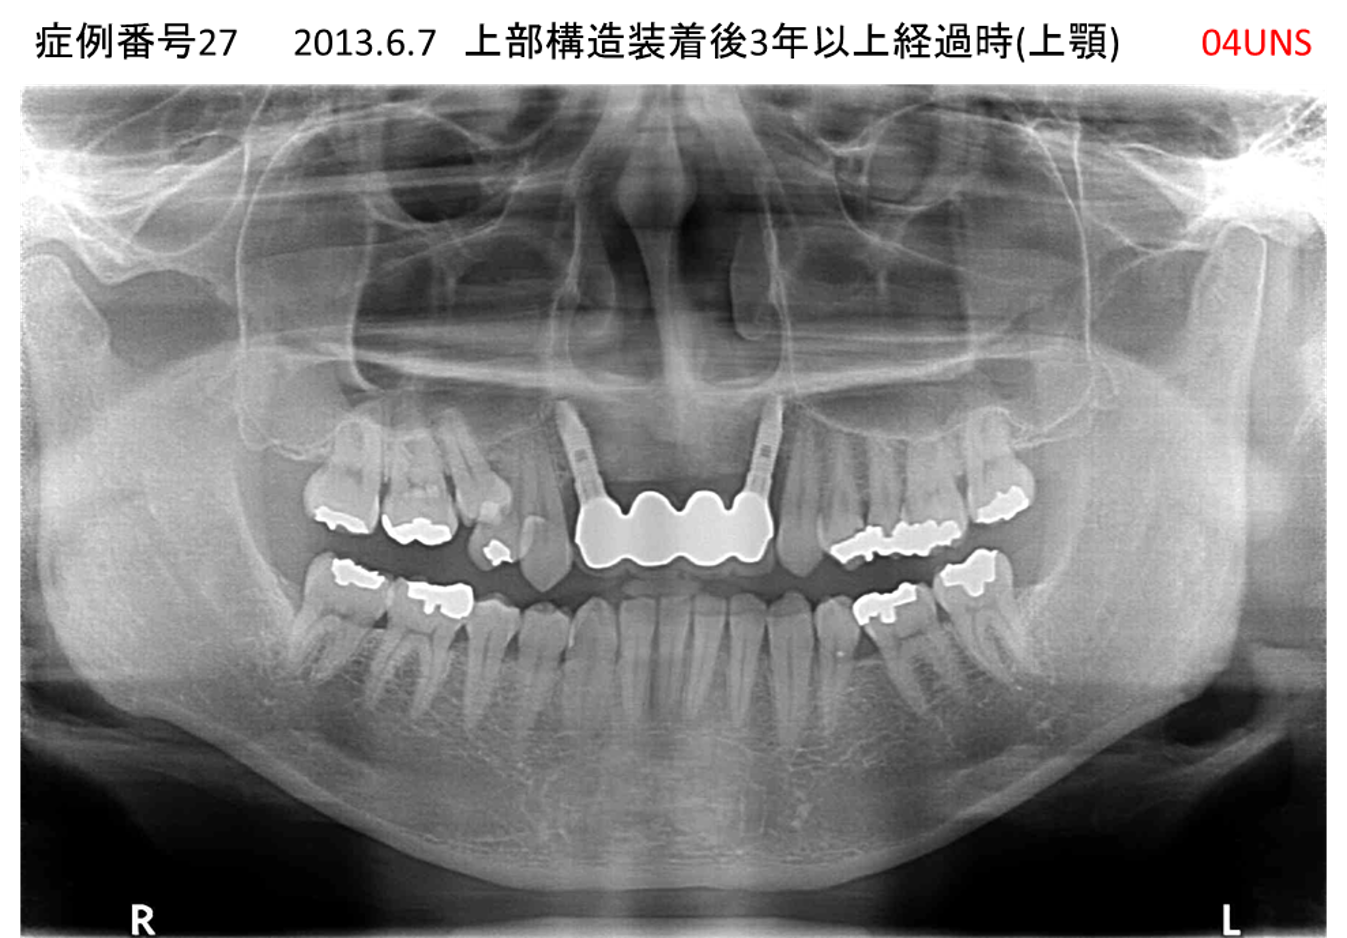

奥歯で噛めない患者様のインプラント症例

| 治療名称 |

インプラント |

| 治療費用 |

365万円+税 |

| 治療期間 |

5か月 |

| 患者さんの症状(主訴) |

奥歯で噛めない。上の前歯が揺れてきた。 |

| 治療内容 |

抜歯即時インプラント |

| 治療結果 |

食事に困らない。見た目がとても良くなった。 |

| 治療の注意点(リスク/副作用) |

インプラントが壊れたら再治療が必要 |